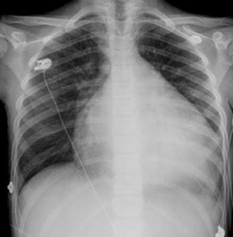

Case number 1: This is a 60-year-old male patient with a history of known hypertension for 10 years controlled with Candesartan plus hydrochlorothiazide 32/25 mg daily. Mixed dyslipidemia controlled with statin type atorvastatin 40 mg daily. Significant central obesity BMI of 35. Also, sedentary life. History of 4 inoculations with the Pfizer vaccine, he began to present with acute respiratory distress, palpitations, paroxysmal nocturnal dyspnea, orthopnea, saturation of 85% by oximetry. On physical examination: marked arterial hypotension 80/60 FC: 135 beats per minute Respiratory rate of 28 per minute acrocyanosis and on cardiac auscultation: rhythm Irregularly irregular with a more audible mitral regurgitation murmur at the apex of the heart radiating to the axilla. Lung auscultation: crackles from the middle third to the base of both lung fields. The electrocardiogram shows rapid atrial fibrillation rhythm at 135 beats per minute. Chest X-ray: Grade III-IV cardiomegaly with acute pulmonary edema. An echocardiogram was performed, showing findings compatible with dilated cardiomyopathy with left ventricular ejection fraction of 10%. Global hypokinesia, in doppler moderate-severe mitral regurgitation. Moderate-severe tricuspid regurgitation with pulmonary systolic pressure of 90 mmHg. Tissue Dopplar significant increase in left intraatrial pressure 25. In addition, the following laboratory analyzes were performed: Complete blood count: leukopenia: 2,000 leucocytes. Hb: 12.5 g/dl. Thrombocytopenia: 107,000 platelets, severe eosinopenia and lymphopenia. Elevated D-dimer 2.0 (normal value up to 0.50) Elevated NtproBNP 3,500 (normal up to 300). C-reactive protein of 32 Normal up to 10. Ferritin of 750 (normal up to 250). Creatinine: 3.2 mg/dl Urea: 70, TGO: 110, TGP:115.

Chest X-ray

1. Findings compatible with dilated cardiomyopathy secondary to graphene hydroxide

2. Severely depressed ejection fraction (10%).

6. Moderate pulmonary arterial hypertension

7. Fast Atrial Fibrillation Rhythm.